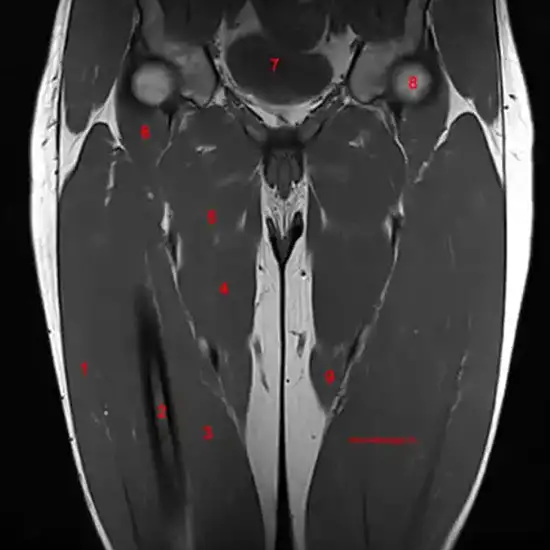

An MRI scan of the right thigh shows the thigh bone, cartilage, tendon, ligaments, muscles, and blood vessels surrounding it.

MRI of the thigh finds leg pain and a broken thigh. This test looks for unusual muscle or soft tissue growth in the thigh.